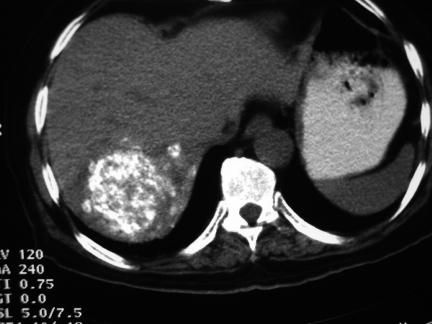

Embolisation has become an accepted modality of cancer treatment in patients with a variety of clinical scenarios. It is commonly used in clinical practice in the treatment of hepatocellular carcinoma, hepatic metastases from colorectal cancer and neuroendocrine tumours, and renal cell carcinoma. This review summarizes the current evidence for the efficacy of embolotherapy in these clinical settings, together with the associated complications.

栓塞治疗已成为多种临床情况下癌症治疗的一种可接受的方式。在临床实践中,它通常用于治疗肝细胞癌、结直肠癌肝转移和神经内分泌肿瘤以及肾细胞癌。本文综述了栓塞治疗在这些临床情况下的疗效的现有证据,以及相关的并发症。